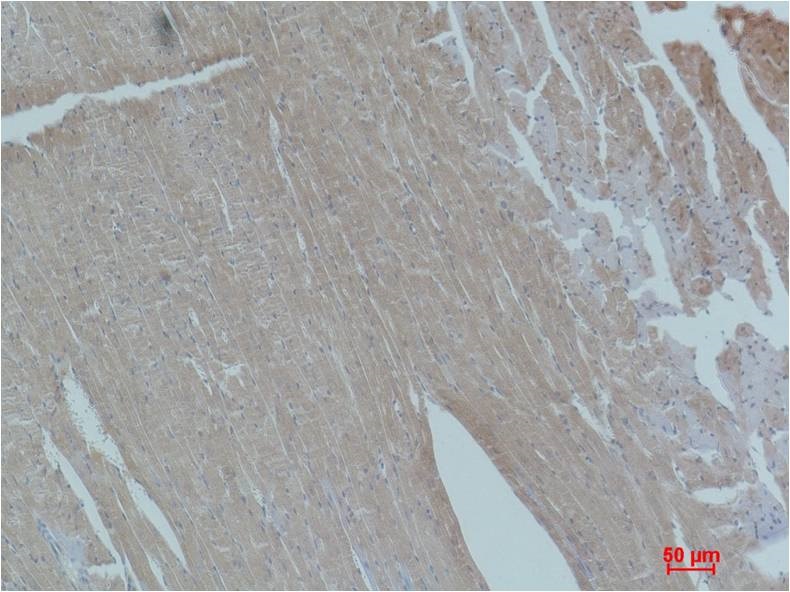

Immunohistochemical analysis of paraffin-embedded Mouse Heart Tissue using Smad2 (BE3420)Rabbit pAb diluted at 1:200